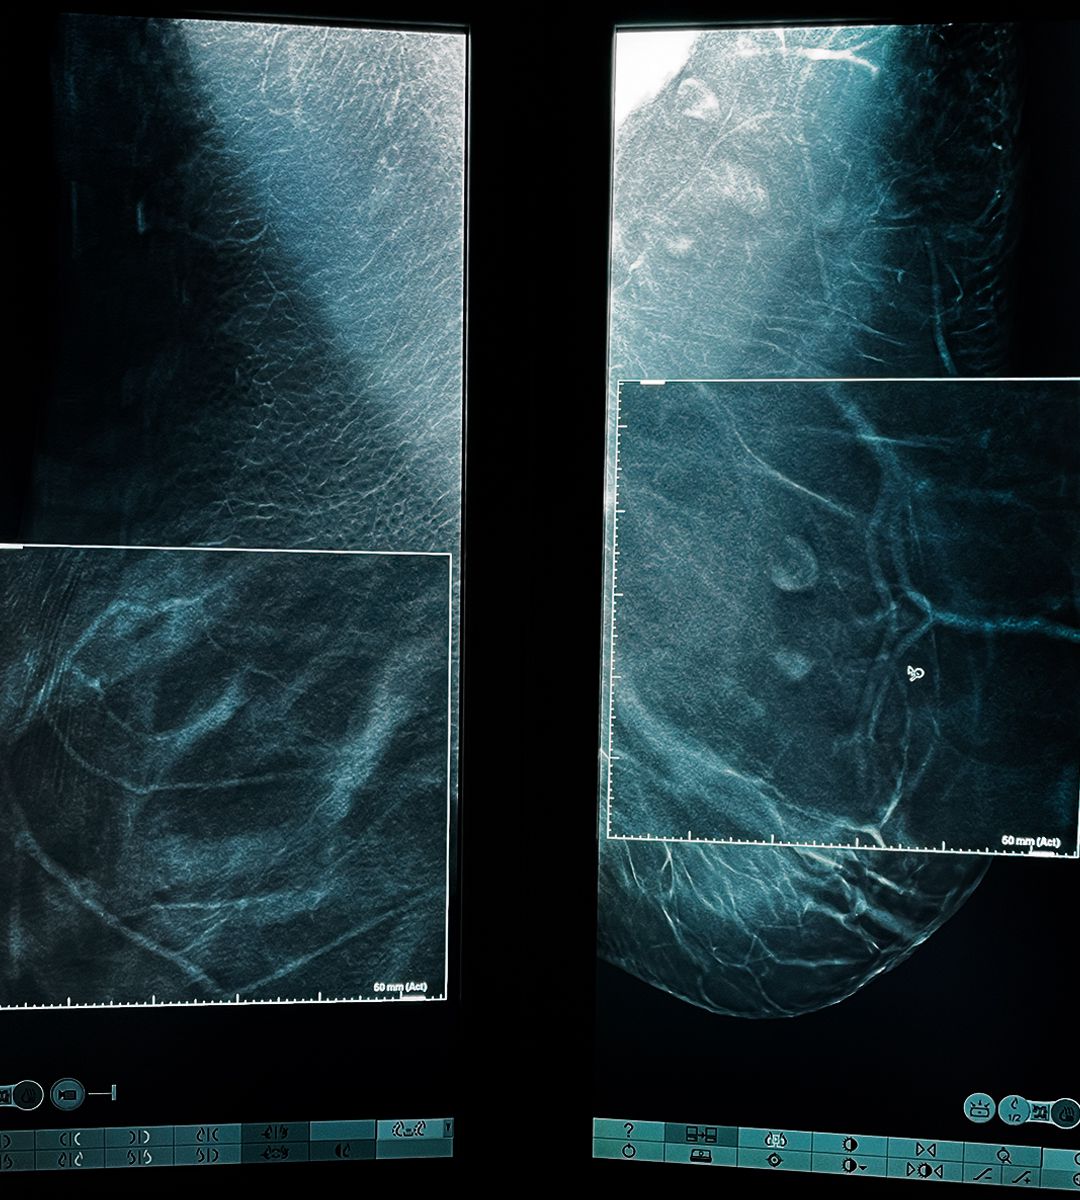

Mamografia digitală 3D sau mamografia cu tomosinteză este o tehnică imagistică ce utizilează raze X pentru a obține imagini detaliate ale sânului în 3 dimensiuni. În timpul unei mamografii digitale 3D, imaginea sânului este capturată în straturi subțiri, oferindu-i medicului posibilitatea de a examina fiecare secțiune în detaliu. Această abordare permite identificarea mai precisă a anomaliilor și a potențialelor leziuni, reducând în acest timp riscul de fals pozitiv sau fals negativ în comparație cu mamografia 2D tradițională.

Tomosinteza este componenta principală a mamografiei digitale 3D, care utilizează o serie de imagini bidimensionale pentru a reconstitui o imagine tridimensională a sânului. Această tehnologie îi permite medicului să examineze fiecare secțiune în detaliu, oferind informații suplimentare și mai precise.

Softul C-View este o tehnică avansată de procesare a imaginilor, care permite generarea unei imagini de înaltă calitate, reducând timpul și expunerea la radiații. De asemenea, acest program optimizează procesul de interpretare a rezultatelor, oferind medicului o imagine clară și detaliată a sânului.

C-View permite obținerea unor imagini 2D prin reconstrucția virtuală a imaginilor 3D. Astfel, medicii pot oferi un diagnostic corect printr-o singură expunere; în cazul mamografiilor digitale cu tomosinteză fără softul C-View, pacienta este expusă la iradiere de două ori.

- Creează o hartă tridimensională (3D) a sânilor, formată din zeci de imagini din profunzimea sânilor (imagini mamografice de 1 mm), din diverse unghiuri, oferindu-i medicului posibilitatea de a pune un diagnostic corect prin faptul că poate examina bucată cu bucată. Prin mamografia clasică 2D medicul putea analiza doar 2 imagini mamografice.

- În aceste imagini din profunzimea sânilor nu apar suprapuneri de țesut așa cum apar în imaginile de mamografie clasică, oferind medicului imagist un grad net superior de acuratețe la depistarea și caracterizarea diferitelor formațiuni și leziuni (distorsiuni arhitecturale, asimetrii – uneori singurul semn de cancer) – în special în cazul sânilor denși.

Datele obținute sunt apoi procesate de un computer pentru a crea o imagine tridimensională. Medicul radiolog examinează imaginile 3D pentru a detecta orice potențiale leziuni sau anomalii. În cazul în care sunt identificate imagini suspecte, medicul va recomanda investigații suplimentare de tipul unui RMN mamar sau al unei biopsii, pentru a confirma diagnosticul și a planifica tratamentul adecvat.